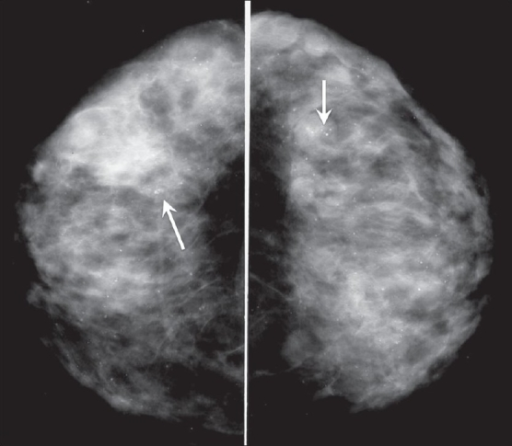

Sclerosing adenosis

This condition is caused by an overgrowth of tissue in the breast lobules. As with radial scars, sclerosing adenosis is generally found on mammogram, as the person will be asymptomatic. It resembles cancer on mammogram and will require further investigation. No treatment is required, but the condition is associated with an increased risk for developing breast cancer.